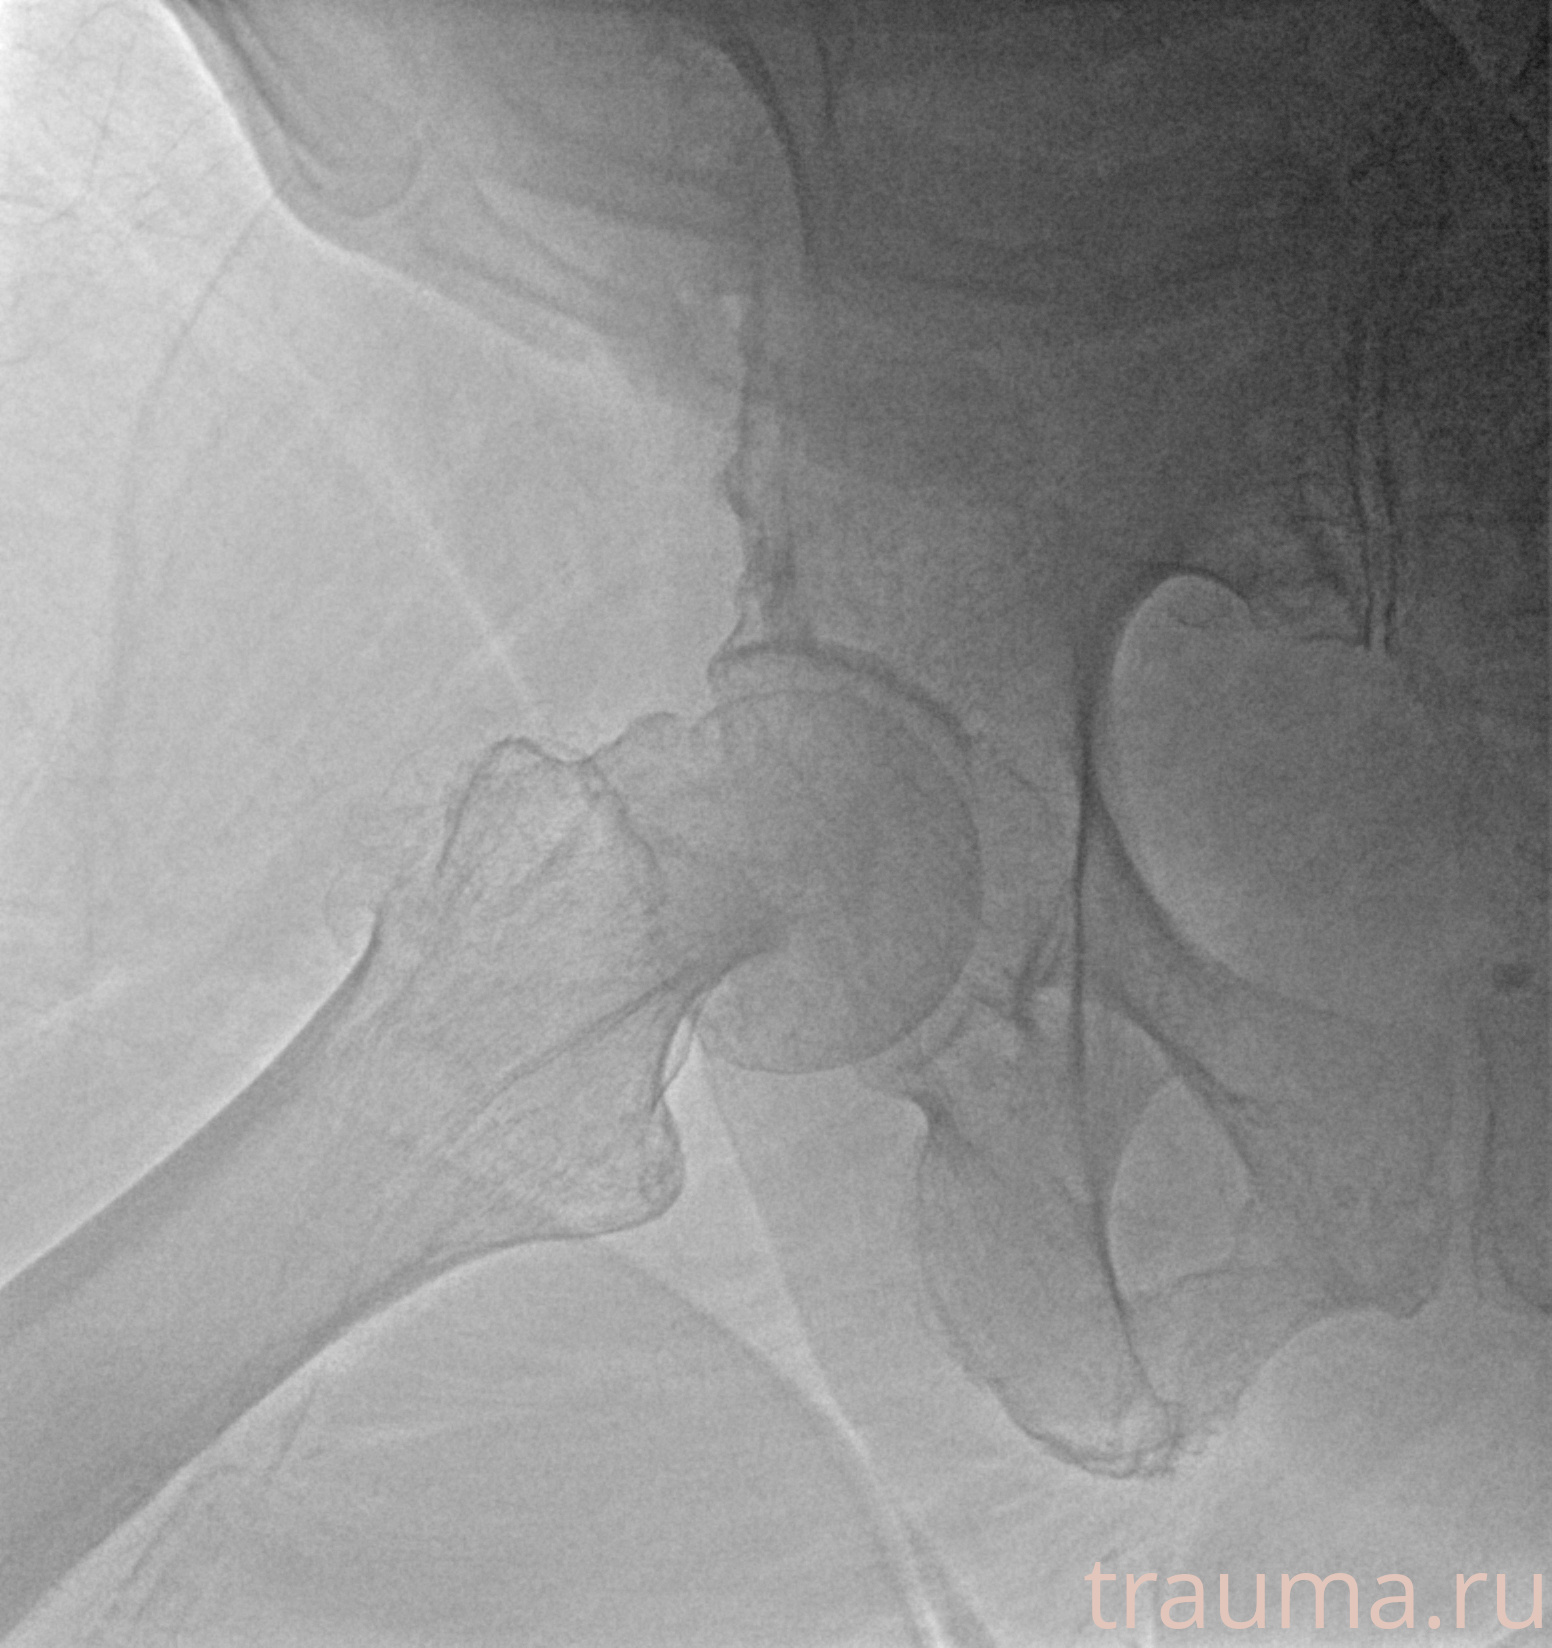

Рентгенограммы

Рентген на дому: по вашему адресу приезжает врач-рентгенолог, травматолог-ортопед с мобильным рентгеновским аппаратом, проводит диагностику травмы или заболевания, делает необходимые рентгенограммы, дает рекомендации по дальнейшему лечению. Получить качественные снимки в домашних условиях возможно благодаря уникальной методике, разработанной МосРентген Центром для института  Склифосовского